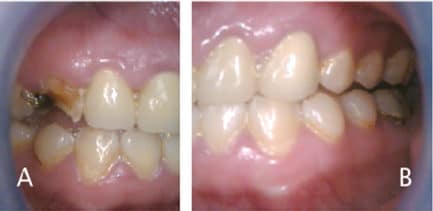

Return to "Managing Cavitated Lesions in Patients Who Abuse Methamphetamine" meth-ce-table-1 Next Previous